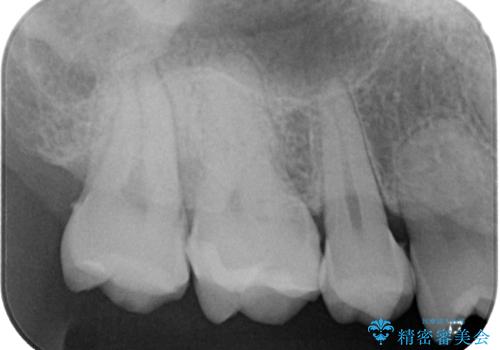

- 金属の詰め物が外れたので、虫歯の治療がしたいとのことで来院された患者様です。ほかの部位の治療などもあったため、コンポジットレジンによる応急処置を初診時に行いました。

ほかの部位の治療が一段落ついたのでセラミックインレー修復による虫歯治療を行っていくことにしました。

歯と歯の間の虫歯の治療について

歯と歯の間の虫歯をコンポジットレジンや保険のメタルインレーで治すと段差ができたりして清掃性が悪くなるので、セラミックインレー修復やゴールドインレー修復などの適合の良い詰め物で治療することをオススメします。